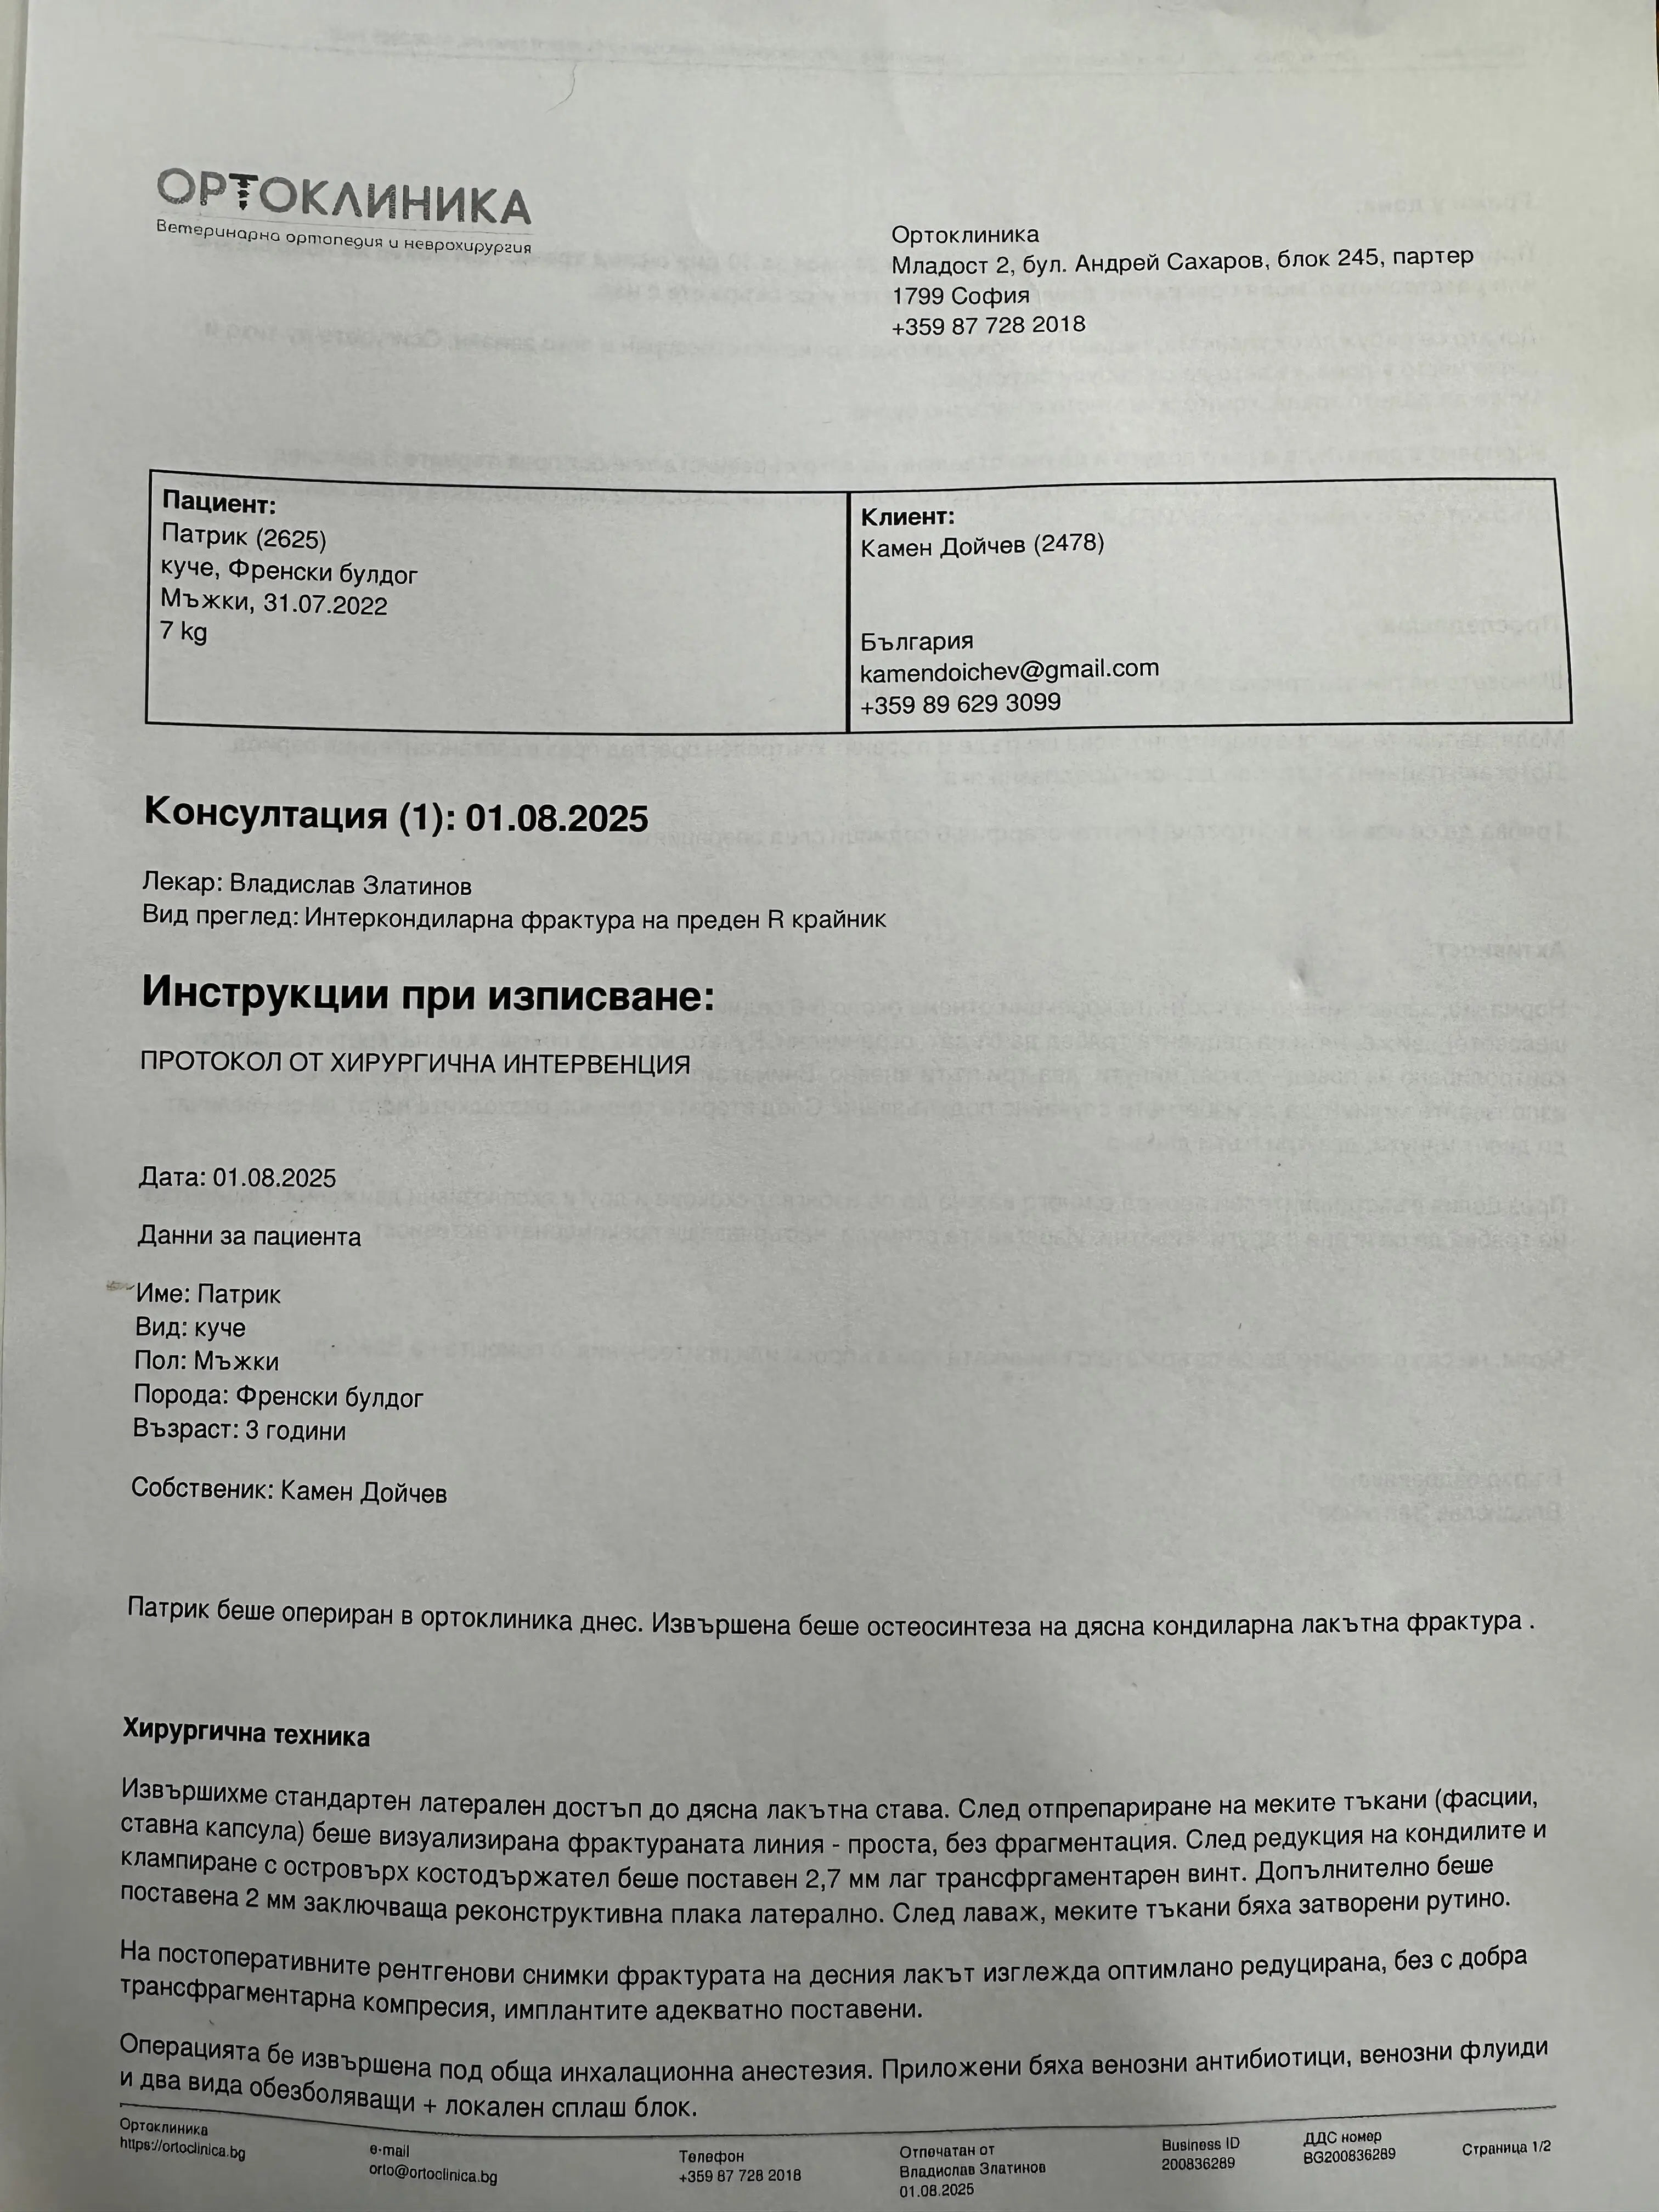

След това беше изгубен за няколко дни, докато го търсих из цяла София – слава Богу, успях да го намеря и веднага го заведох на ветеринар. Рентгеновите снимки показаха счупване, което изискваше спешна операция.

Направихме я в Ортоклиник,гр. София, където се отнесоха с голямо разбиране и ми позволиха да платя разсрочено.

Цялата сума на операцията е 1900 лева, от които аз заплатих 1000 и в момента трябва да събера останалата част от 900 лева до края на месец Август.

He was then lost for a few days while I searched all over Sofia for him - thank God I managed to find him and immediately took him to the vet. X-rays showed a fracture that required emergency surgery.

We did it in Orthoclinic,gr. They were very understanding and allowed me to pay in installments.

The total amount of the operation was 1900 leva, of which I paid 1000 and now I have to collect the rest of 900 leva by the end of August.